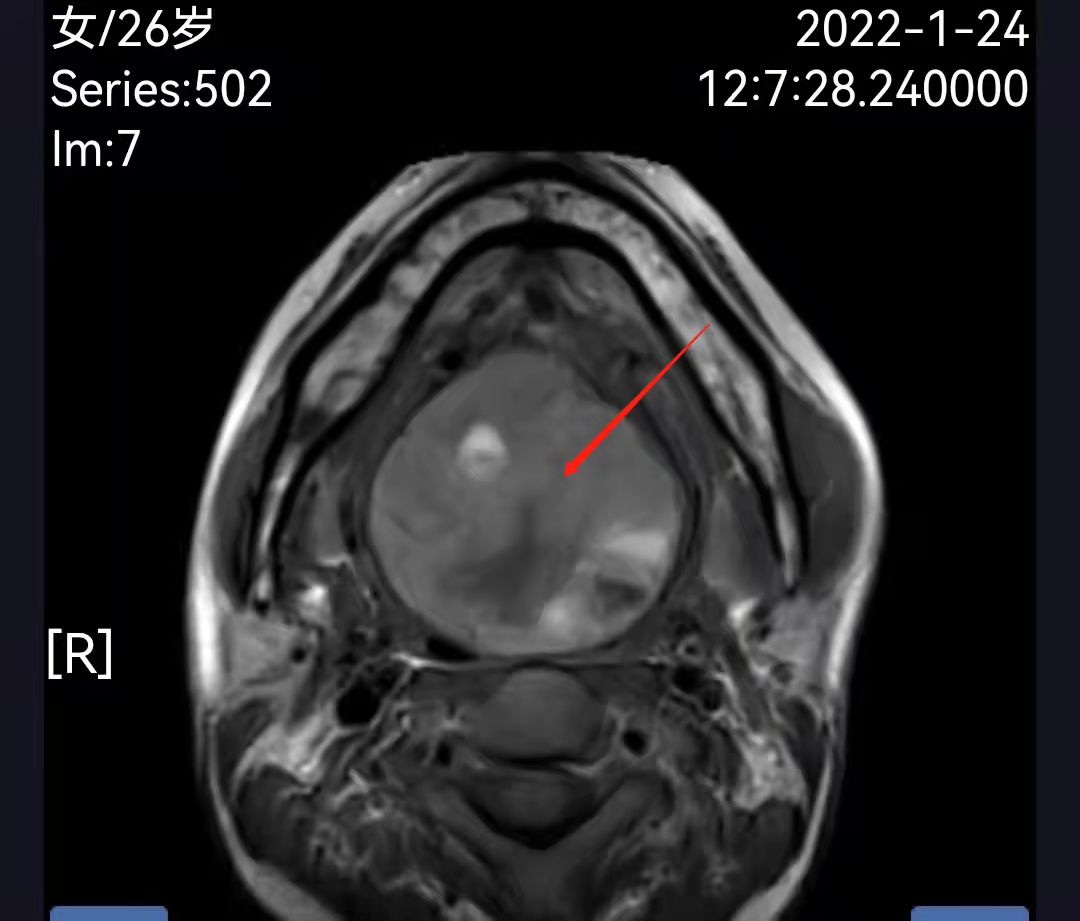

26岁的孕妇谭女士,妊娠28周,年少时曾做过一次甲舌囊肿手术,两年前在一家大医院诊断出“异位甲状腺并血管畸形”,因手术风险大一直保守治疗。患者怀孕后出现甲状腺功能低下合并反复口咽部活动性出血,随孕期增长,出血频率越来越多出血量越来越大,每次达200-300ml,多方就医均因保胎风险太大未行手术。近期舌根部肿瘤迅速长大,患者出现说话含糊、呼吸困难症状,最近一次出血量达500ml,命悬一线,患者被紧急转往湘雅三医院耳鼻喉科急诊入院。

患者入院后口咽部仍反复多次出现活动性出血,每次量约200ml,经检查,患者不仅患有“异位甲状腺合并滤泡腺瘤”,且伴有“颈部血管畸形”,畸形血管的脆性极大,随时都有大出血和窒息的风险,孕妇和胎儿都面临极大的生死考验。谭国林教授团队立即组织麻醉科、产科、内分泌、营养科、临床药学等多学科会诊,充分评估手术风险,制定个体化的诊疗方案,入院后即积极完善术前准备,予以输血和营养改善,提高手术耐受性;在产科指导下使用糖皮质激素,促进胎儿肺泡的成熟,以应对万一早产的风险;临床药学和麻醉科拟订最佳麻醉方案,减少麻醉用药对孕妇和胎儿带来的影响;营养科指导留置胃管,术后及早予以肠内营养,保证营养供给。